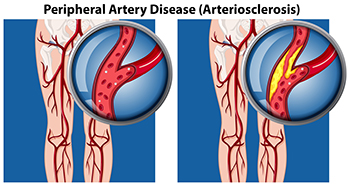

Peripheral arterial disease (PAD) occurs when the outer, or peripheral, arteries narrow due to a build-up of plaque. Peripheral arteries transport blood—which carries oxygen and nutrients—to the legs and arms, keeping the skin and underlying tissue alive and healthy. When PAD is present in the legs, it can reduce the normal amount of blood flow, oxygen, and nutrients to the feet. This may lead to dysfunction in the skin and tissue, causing it to break down and make it more susceptible to developing wounds. PAD can be an inherited disease, or may be caused by diabetes, hypertension, high cholesterol, or obesity. Symptoms of PAD in the feet may include burning, aching, coolness, redness, reoccurring infections, and sores in the toes and feet that do not heal. If you are experiencing any of these symptoms, contact a podiatrist for a full examination, testing, diagnosis and proper treatment.

Peripheral artery disease (PAD) is when arteries are constricted due to plaque (fatty deposits) build-up. This results in less blood flow to the legs and other extremities. The main cause of PAD is atherosclerosis, in which plaque builds up in the arteries.

Symptoms

Symptoms of PAD include:

- Claudication (leg pain from walking)

- Numbness in legs

- Decrease in growth of leg hair and toenails

- Paleness of the skin

- Erectile dysfunction

- Sores and wounds on legs and feet that won’t heal

- Coldness in one leg

It is important to note that a majority of individuals never show any symptoms of PAD.

Diagnosis

While PAD occurs in the legs and arteries, Podiatrists can diagnose PAD. Podiatrists utilize a test called an ankle-brachial index (ABI). An ABI test compares blood pressure in your arm to you ankle to see if any abnormality occurs. Ultrasound and imaging devices may also be used.

Treatment

Fortunately, lifestyle changes such as maintaining a healthy diet, exercising, managing cholesterol and blood sugar levels, and quitting smoking, can all treat PAD. Medications that prevent clots from occurring can be prescribed. Finally, in some cases, surgery may be recommended.